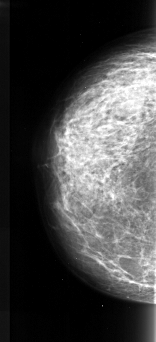

A_1023_1.RIGHT_MLO

RIGHT_CC LINES 5011 PIXELS_PER_LINE 2701 BITS_PER_PIXEL 16 RESOLUTION 42 NON_OVERLAY